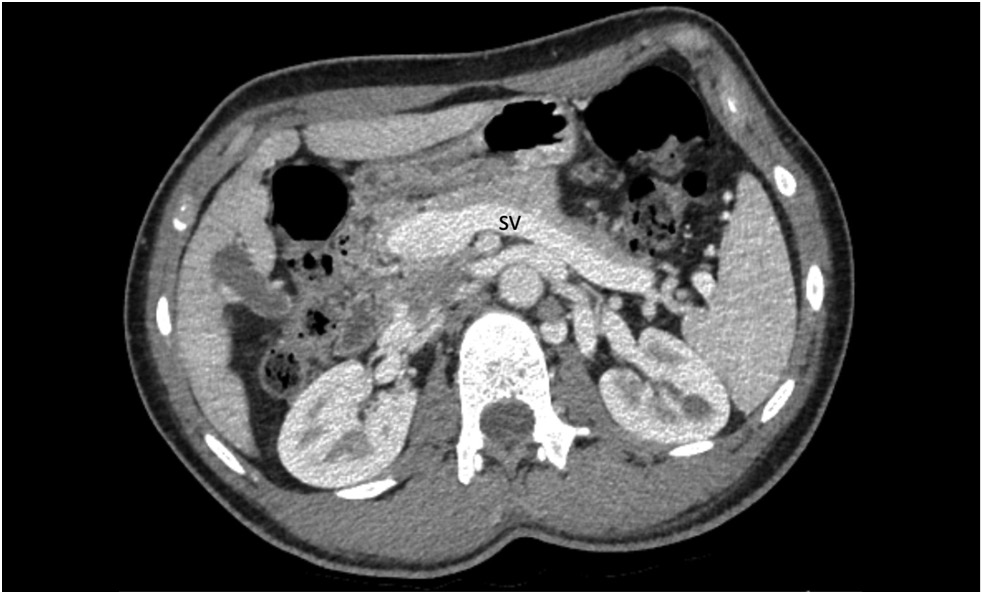

A 15-year-old male with a history of chronic epigastric pain and nausea, high arterial blood pressure, recurrent nose bleeds, chest pain, dizziness, dyspnea, low exercise tolerance, hematochezia, and itching was diagnosed with Abernethy malformation type Ib. Imaging studies revealed a dilated portal vein conduit flowing into the inferior vena cava, bypassing the porta hepatis. Multiple liver nodules, heart chamber dilatation, myocardial hypertrophy, and pulmonary hypertension were also discovered. Following multidisciplinary panel meetings, liver transplantation was advised due to the severity of the patient’s symptoms and shunt anatomy.